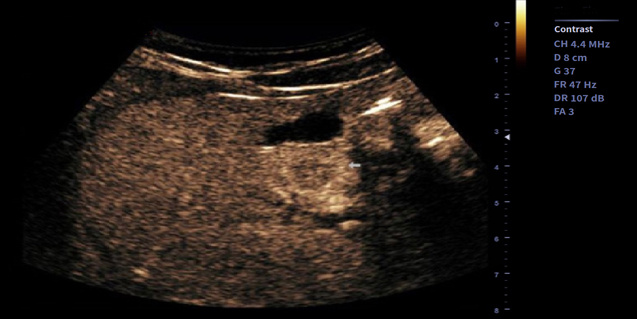

适用于腹部,妇产,泌尿等